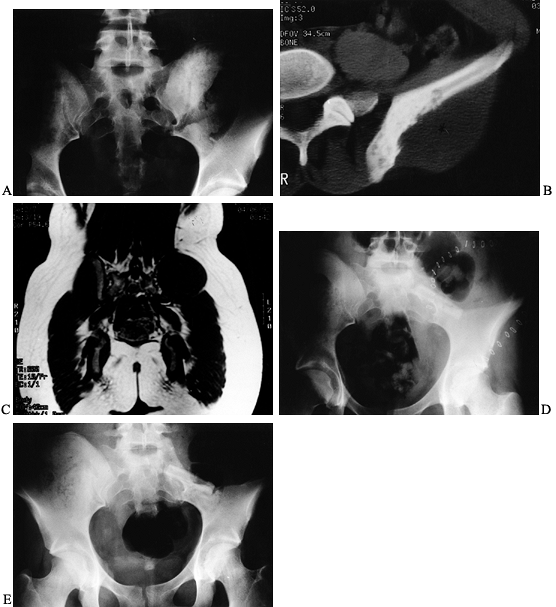

|

Figure 126.10. A: AP radiograph of the knee and proximal tibia from a 15-year-old boy. An osteosarcoma involves the upper tibia. B: Lateral radiograph of tibial osteosarcoma. C:

AP radiograph after resection of the upper tibia (intra-articular) and allograft arthrodesis. Note the intramedullary rod and screws for fixation. D: Lateral radiograph showing fusion of the knee. |